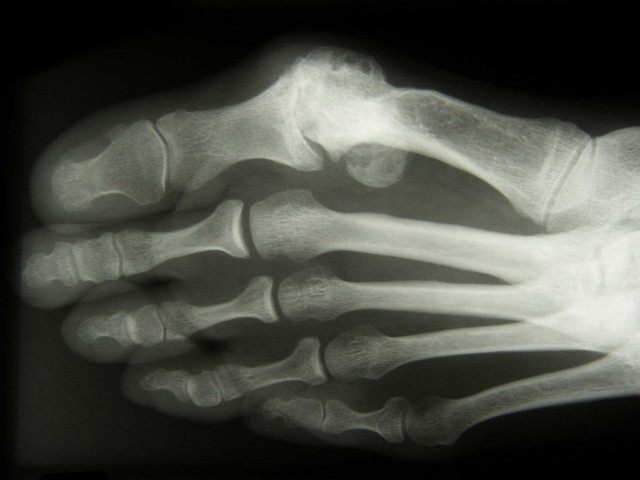

In unserem Bewegungsapparat genießen unsere Füße daher auch eine ganz besondere Aufmerksamkeit. Doch die zahlreichen Belastungen und das Gewicht, das sie jeden Tag aufs Neue tragen müssen, können die Füße überfordern und zu Beschwerden verschiedenster Art führen. Dabei können diese sowohl den Gelenken als auch den Sehnen und Muskeln geschuldet sein. In jedem Fuß steckt eine beeindruckende Kette aus unterschiedlichsten Gelenken. Die komplexe Gelenkkette schließt zahlreiche Knochen ein. Damit diese Hand in Hand arbeiten und eine sichere und komfortable Beweglichkeit ermöglichen, werden sie durch verschiedene Muskeln, Sehnen und Bänder stabilisiert.

Es gibt aber auch viele Fußdeformitäten sowie Erkrankungen bei Patienten der Fußchirurgie in Düsseldorf, bei denen operative Maßnahmen unvermeidbar sind, um Beschwerden erfolgreich zu behandeln. Ziel der Fußchirurgie in Düsseldorf ist es, Ihnen ein schmerz- und beschwerdefreies Gehen zu ermöglichen. Durch die Korrektur und Beseitigung von Deformitäten können wir aktiv Einfluss auf bestimmte Erkrankungen nehmen und deren Verlauf sehr positiv gestalten. Wir bauen bei der Fußchirurgie in Düsseldorf auf die Anwendung moderner Operationsverfahren, mit denen wir unseren Patienten eine Behandlung nach höchstem Qualitätsstandard anbieten. Besondere Bedeutung besitzen dabei der Erhalt der Gelenke und deren Funktion.